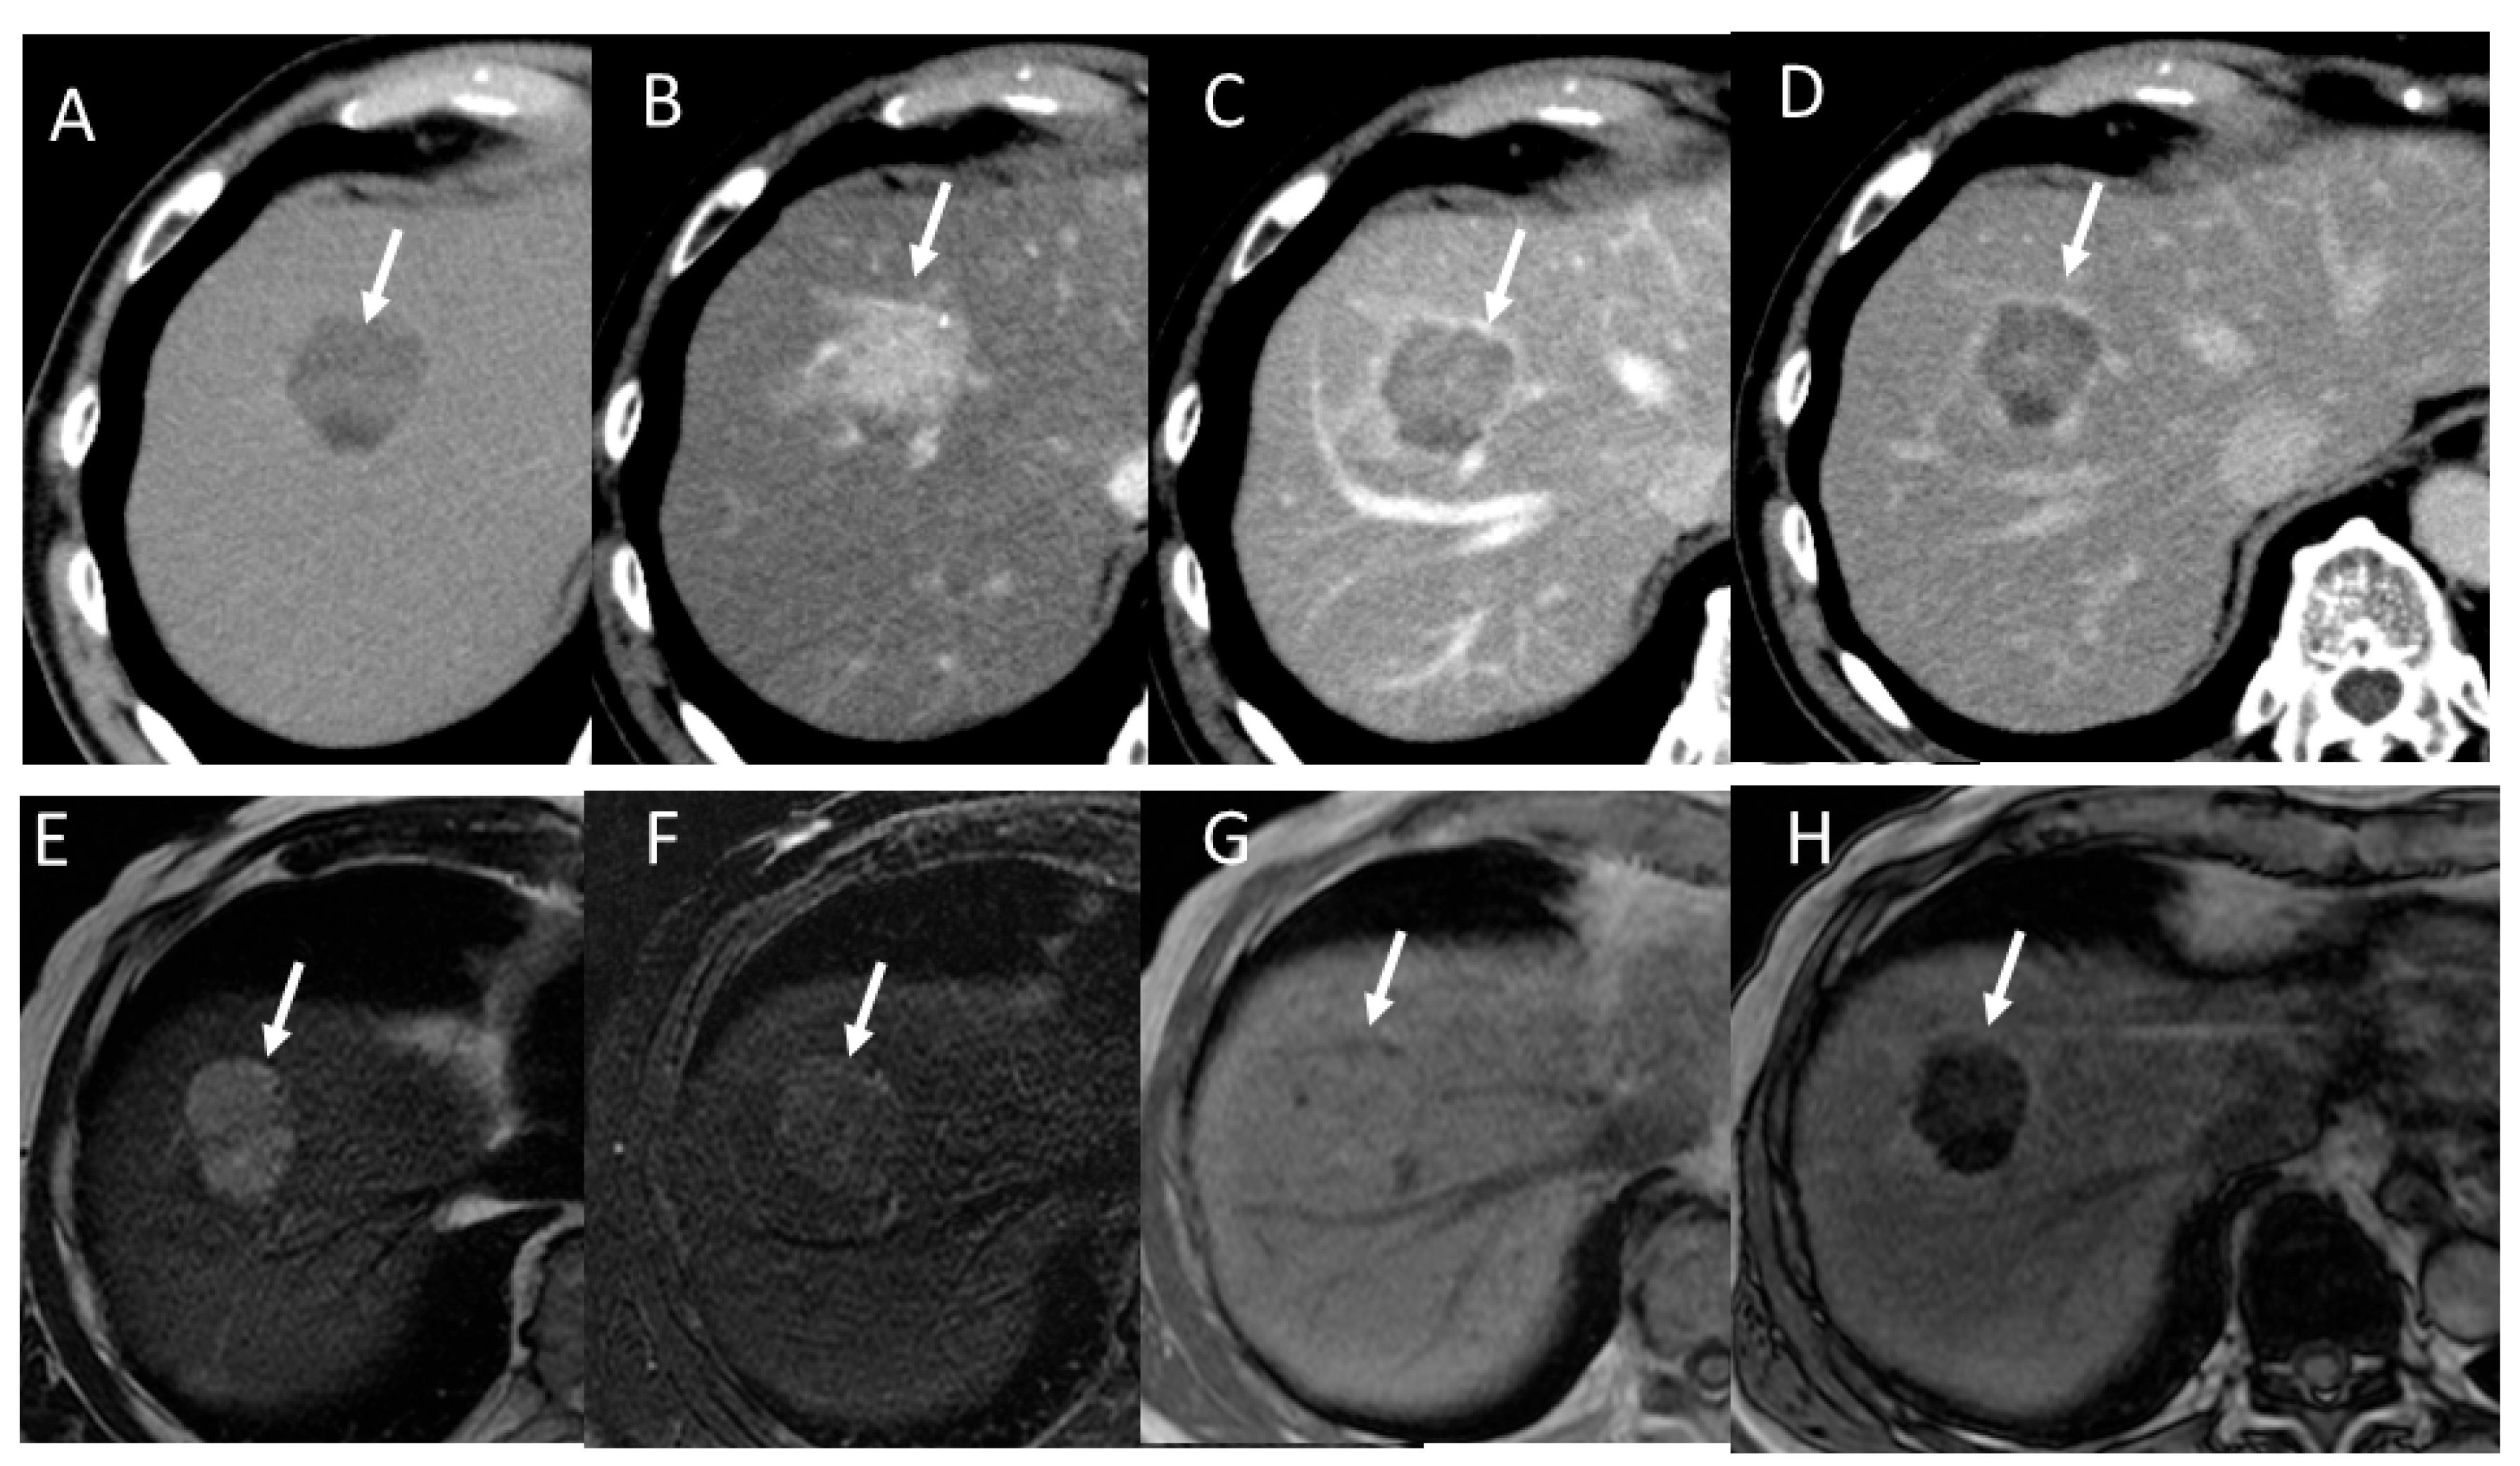

2.1. HCC Imaging on CT

2.2. HCC Imaging on MRI

4.2. Early Hepatocellular Carcinoma (Early-HCC)

4.3. Well-Differentiated Hepatocellular Carcinoma (Well-HCC)

4.4. Moderately Differentiated Hepatocellular Carcinoma (Moderately HCC)

4.5. Poorly Differentiated Hepatocellular Carcinoma (Poorly HCC)